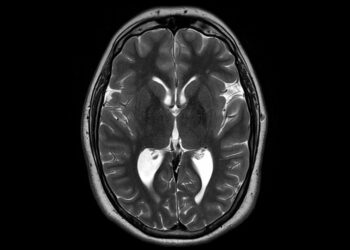

Kepenų siurbikė (fascioliazė): priežastys, simptomai ir gydymas

Kepenų siurbikės – tai parazitiniai kirmėliai, kurie apsigyvena žmogaus kepenyse, tulžies pūslėje arba tulžies latakuose, pažeisdami šiuos organus. Šie parazitai...